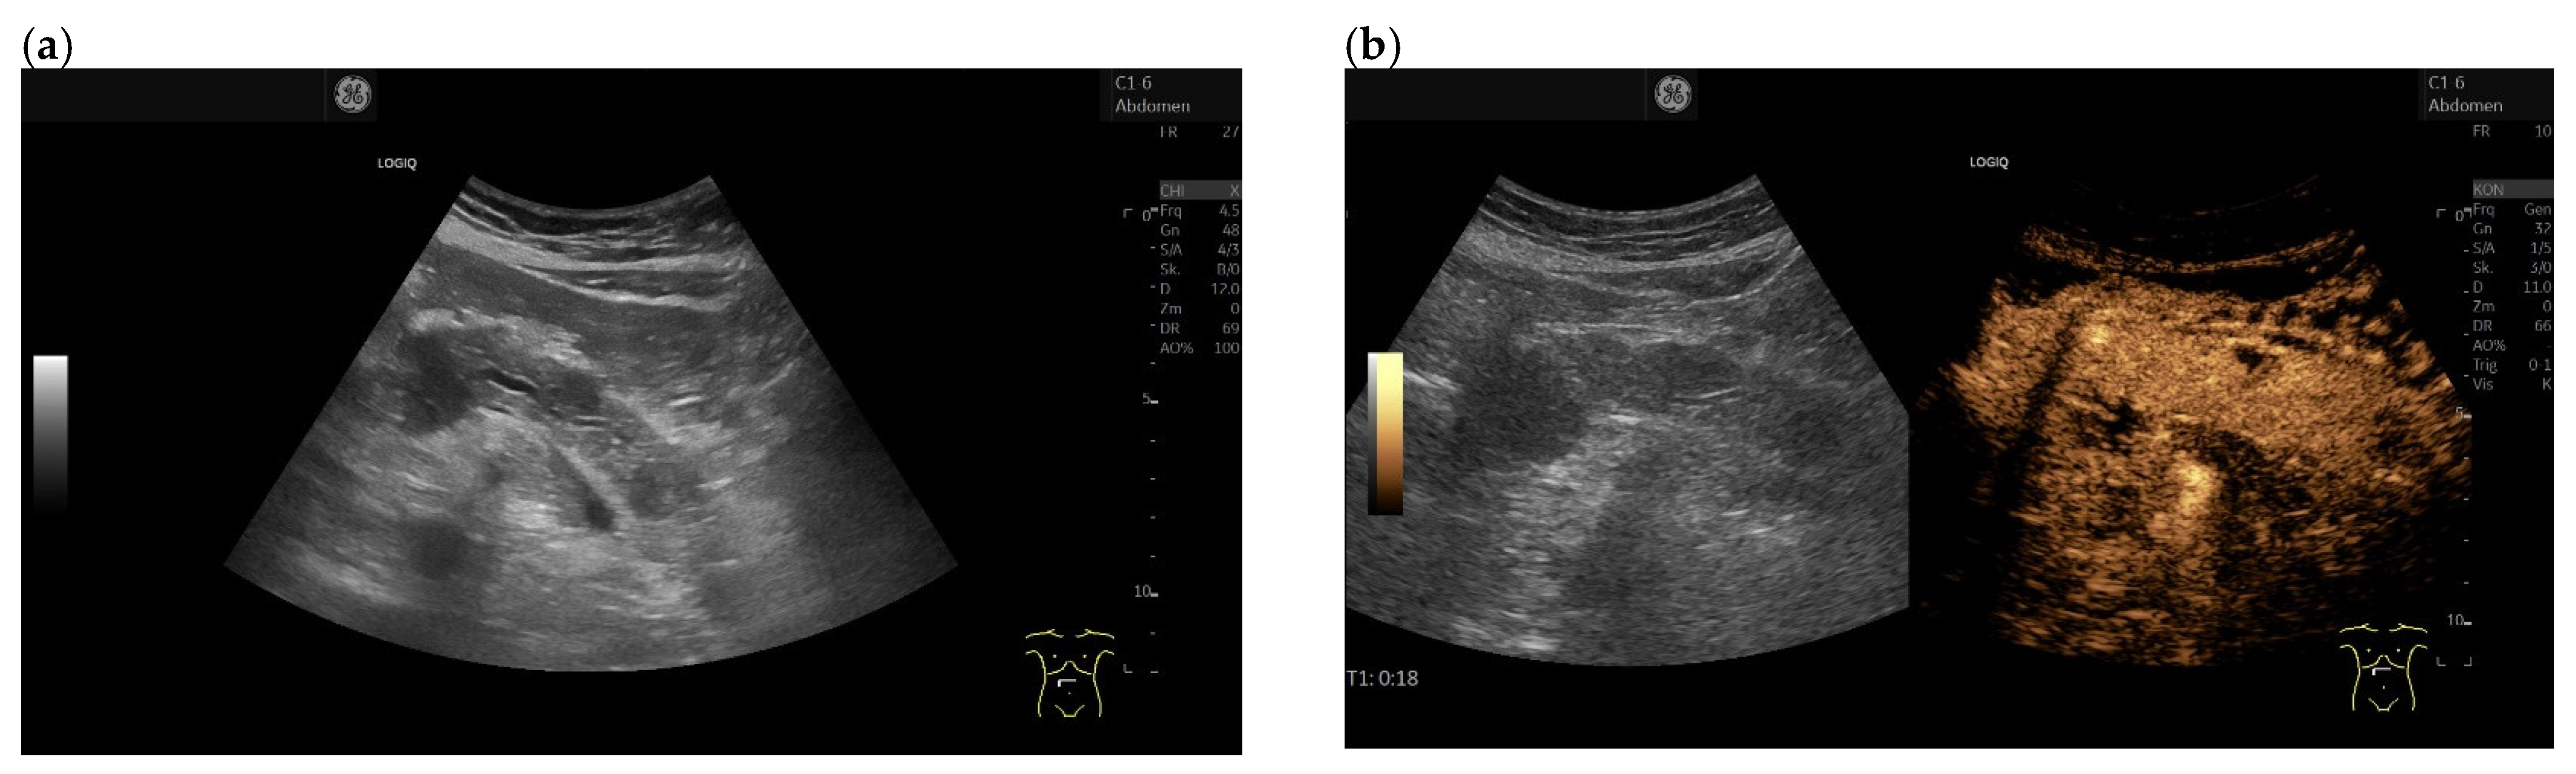

3.4. CEUS and CH-EUS

| Colour Doppler Imaging | RCC metastases are hypervascularized Most other pancreatic metastases are hypovascularized | No hypervascularization | Hypervascularized |

| Cases | CEUS | CH-EUS | ||

|---|---|---|---|---|

| Arterial Phase | Venous Phase | Arterial Phase | Venous Phase | |

| RCC metastases [83] (n = 4) | Hyperenhancement, Early | Hyperenhancement | ||

| RCC metastases [61] (n = 3) | Hyperenhancement, homogeneous pattern | Slow washout | ||

| RCC metastasis [86] (n = 1) | Hyperenhancement, Inhomogeneous pattern | No washout | ||

| Melanoma metastasis [63] (n = 1) | Iso- to slightly hypoenhanced | Hypoenhanced | ||

| Melanoma metastasis [87] (n = 1) | Isoenhanced | Hypoenhancement of the peripheral rim, central non-enhancement | ||

| Melanoma metastasis [61] (n = 1) | Isoenhanced, heterogeneous | Fast washout | ||

| SCLC metastasis [83] (n = 1) | Hyperenhancement | Rapid washout | ||

| Breast, ovarian, colon metastases, sarcoma metastases [61] (n = 6) | Hypoenhancement, homogeneous or heterogeneous | Fast or slow washout | ||

| Lymphoma metastasis [61] (n = 1) | Hyperenhancement, homogeneous pattern | Fast washout |